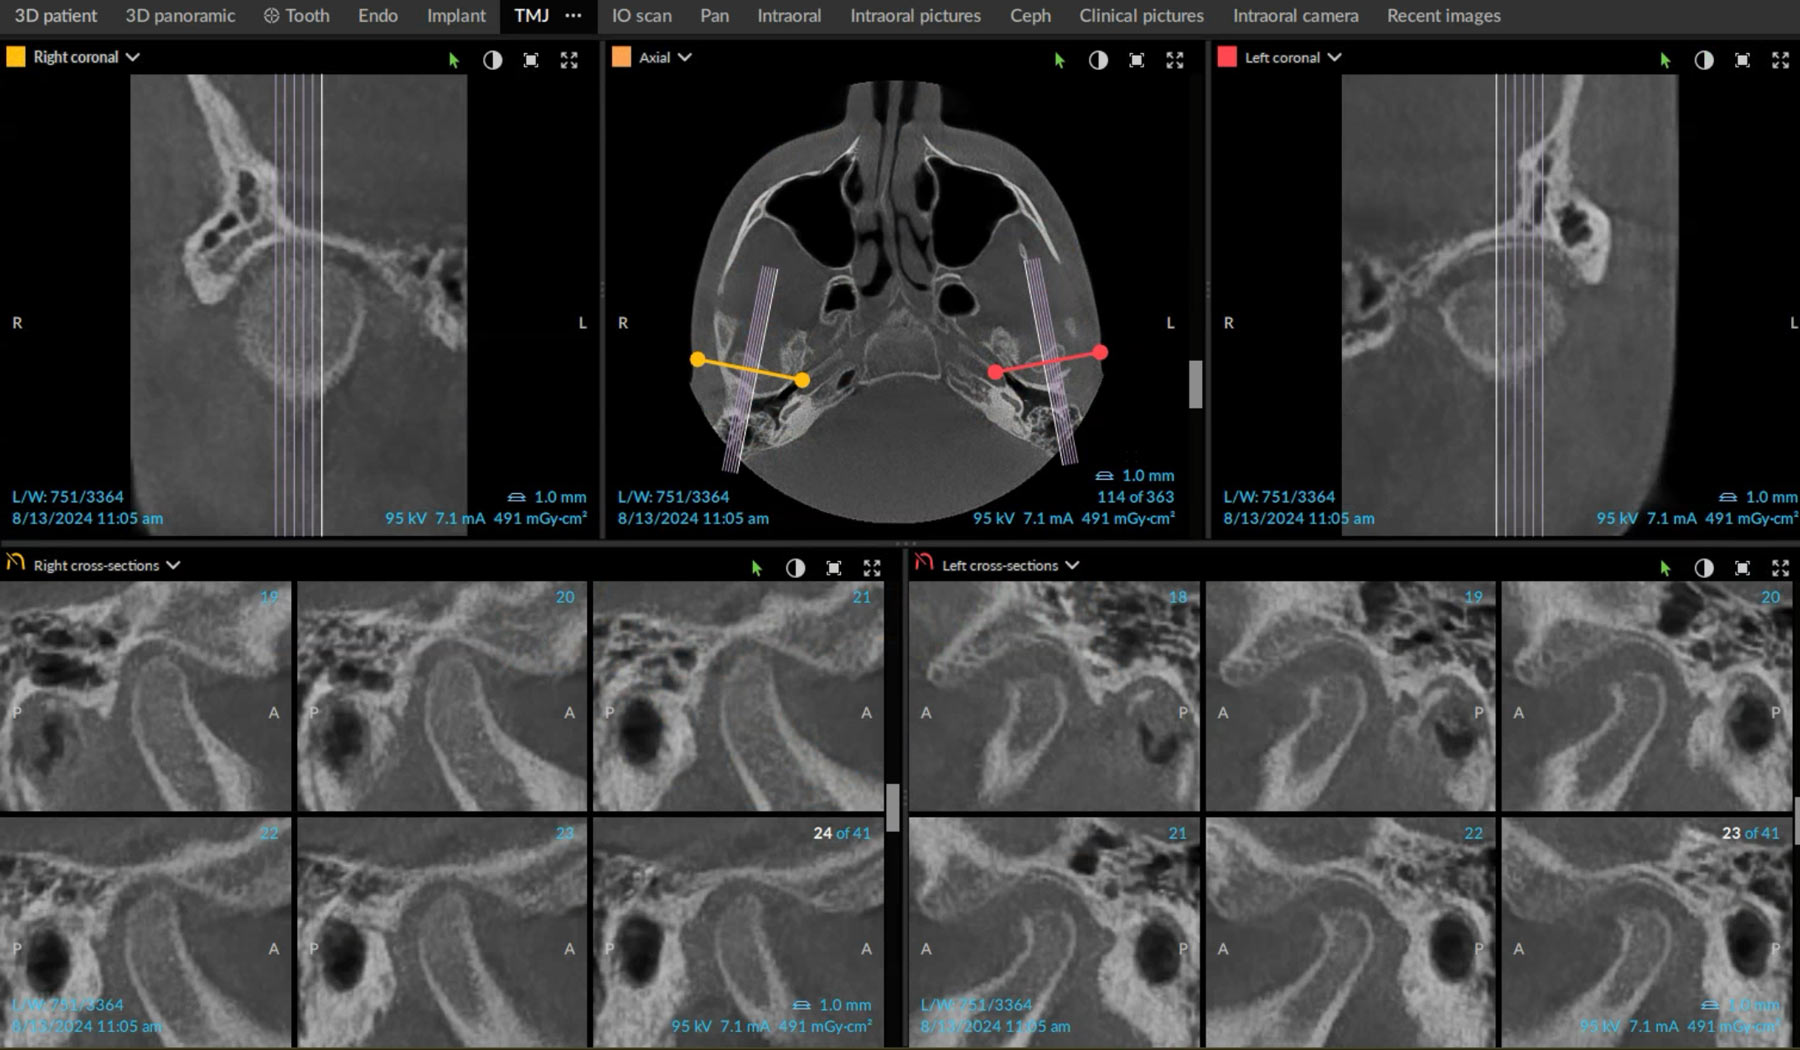

Understanding the TMJ:

TMJ stands for temporomandibular joint and is the hinge joint that connects the jawbone to the skull. The TMJ consists of bones, muscles, ligaments, and a small disc that cushions the joint to allow smooth jaw movement. Located on each side of the head in front of the ears, the pair of TMJ joints function in synchronized harmony allowing for smooth movements of the lower jaw.

TMJ Disorders (TMD):

Studies show that temporomandibular disorders (TMD) are common in the pediatric and teen groups and can manifest in three main ways:

- Disorders of the joints, including disc disorders.